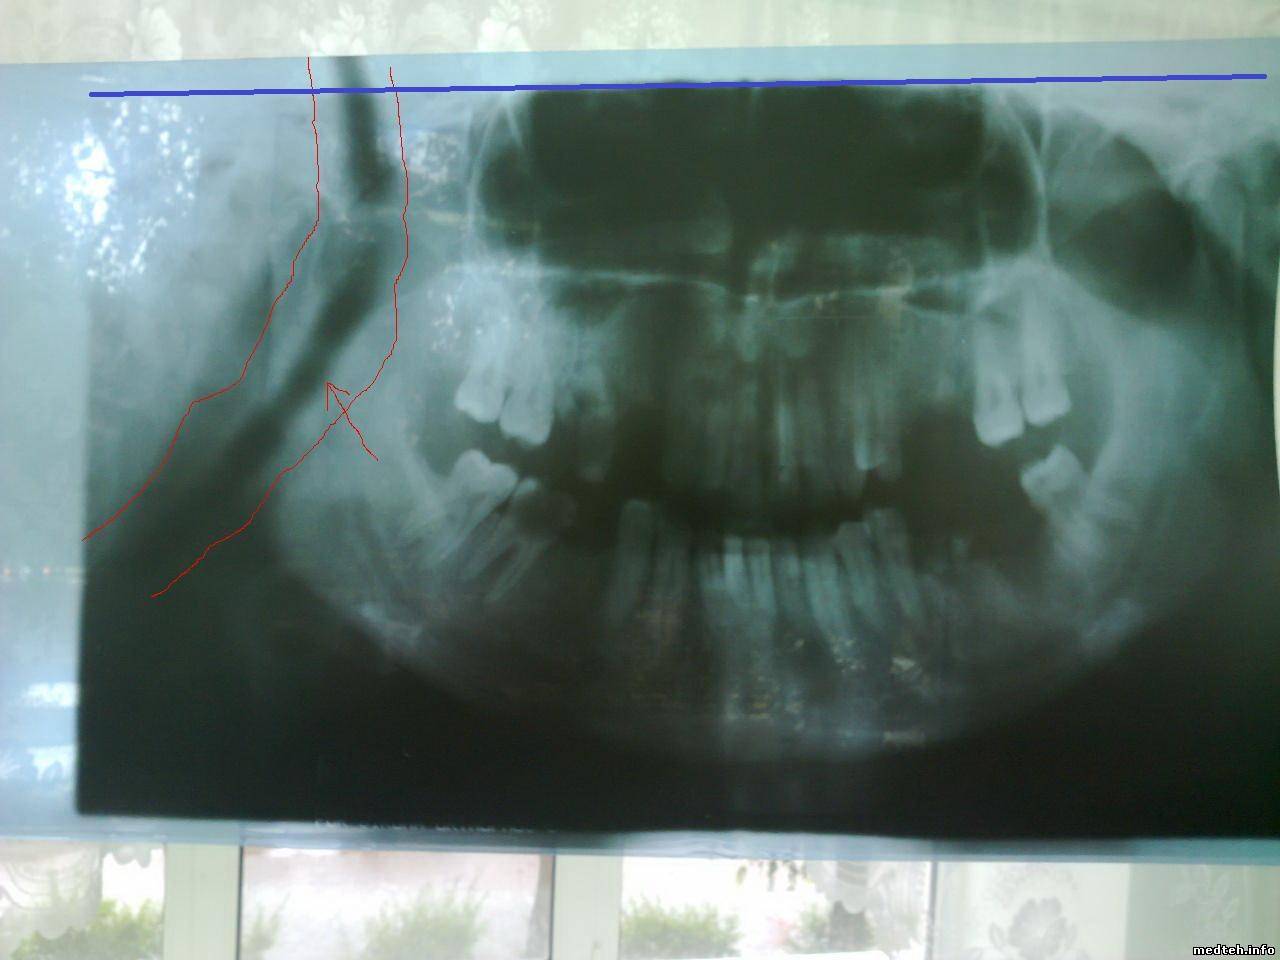

если не совсем понятно, еще могу найти снимки. это на первой программе сделано.

1279257.jpg (67.0 Kb) · 7272345.jpg (68.9 Kb)

Первое, что приходит на ум, это что выбранна программа не для всей челюсти. если коротко, то есть несколько программ для панорамной сьемки. пример: съемка суставов челюсти; съемка всей челюсти; сьемка передней части челюсти ; и т.д.

неее, там 1 программа- обычная панорамная съемка, 11- панорамная съемка при 1,3-кратном увеличении, 6.1и 6.2-съемка суставов.

вот снимок что на фото- это 1 программа. В снимок то все входит, как на нормальном панорамном. вот почему он получается зауженным, я не понимаю. При чем с слева и справа одинаковое расстояние. время экспозиции-11 с., то есть как положено.

зауженный снимок у тебя симметричный, почему-бы - факт что так и должно быть

снимок панорамный - значит с одной стороны начало снимка зависит от времени задержки и начала высокого плюс скорость перемещения кассеты, вторая сторона зависит от той же скорости и времени экспозиции

Интересно почему на снимках правая сторона черная (засвечена), а левая белая (нет высокого)?

Получается надо регулировать начало и конец подачи высокого.

И увеличивать скорость движения кассеты.

По поводу почернения на правой стороне мне вообще непонятно, после этого почернения следует белая"прожилка", то есть как будто выключено высокое , и снова включается когда начинается снимок. примерно 3 мм- "прожилка". хотя во время сьемки луч не выключается.